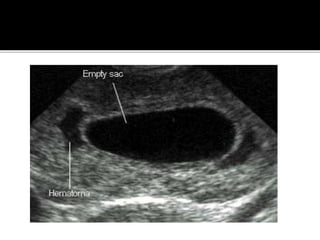

 A subchorionic haemorrhage is often seen,

but unless large does not carry a poor

prognosis.

 Features which do predict poor outcome

include:

• Fetal bradycardia : < 80 - 90 bpm

• Small or Irregular Gestational Sac : MSD -

CRL < 5 mm

• Large Subchorionic Haemorrhage